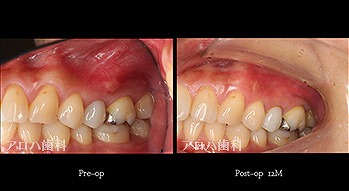

頬側に瘻孔

case9

自費の補綴